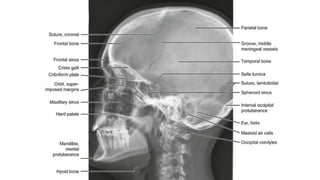

Lateral view

 It is a non angled lateral radiograph of the skull.

It provides an overview of all the sinuses.

 The sagittal midline of the patient’s head is

parallel to the image detector.

 The beam travels laterally, with 0 of

⁰

angulation, through a point 4cm above the

EAC.

• collimation

• superiorly to include skin margins

• inferiorly to include base of skull

• anteriorly to include frontal bone

• posteriorly to the skin margins

Air fluid levels seen on lateral view indicating skull base fracture

z Lateral view  Itis a non angled lateral radiograph of the skull. It provides an overview of all the sinuses.  The sagittal midline of the patient’s head is parallel to the image detector.  The beam travels laterally, with 0 of ⁰ angulation, through a point 4cm above the EAC. • collimation • superiorly to include skin margins • inferiorly to include base of skull • anteriorly to include frontal bone • posteriorly to the skin margins

Air fluid levelsseen on lateral view indicating skull base fracture